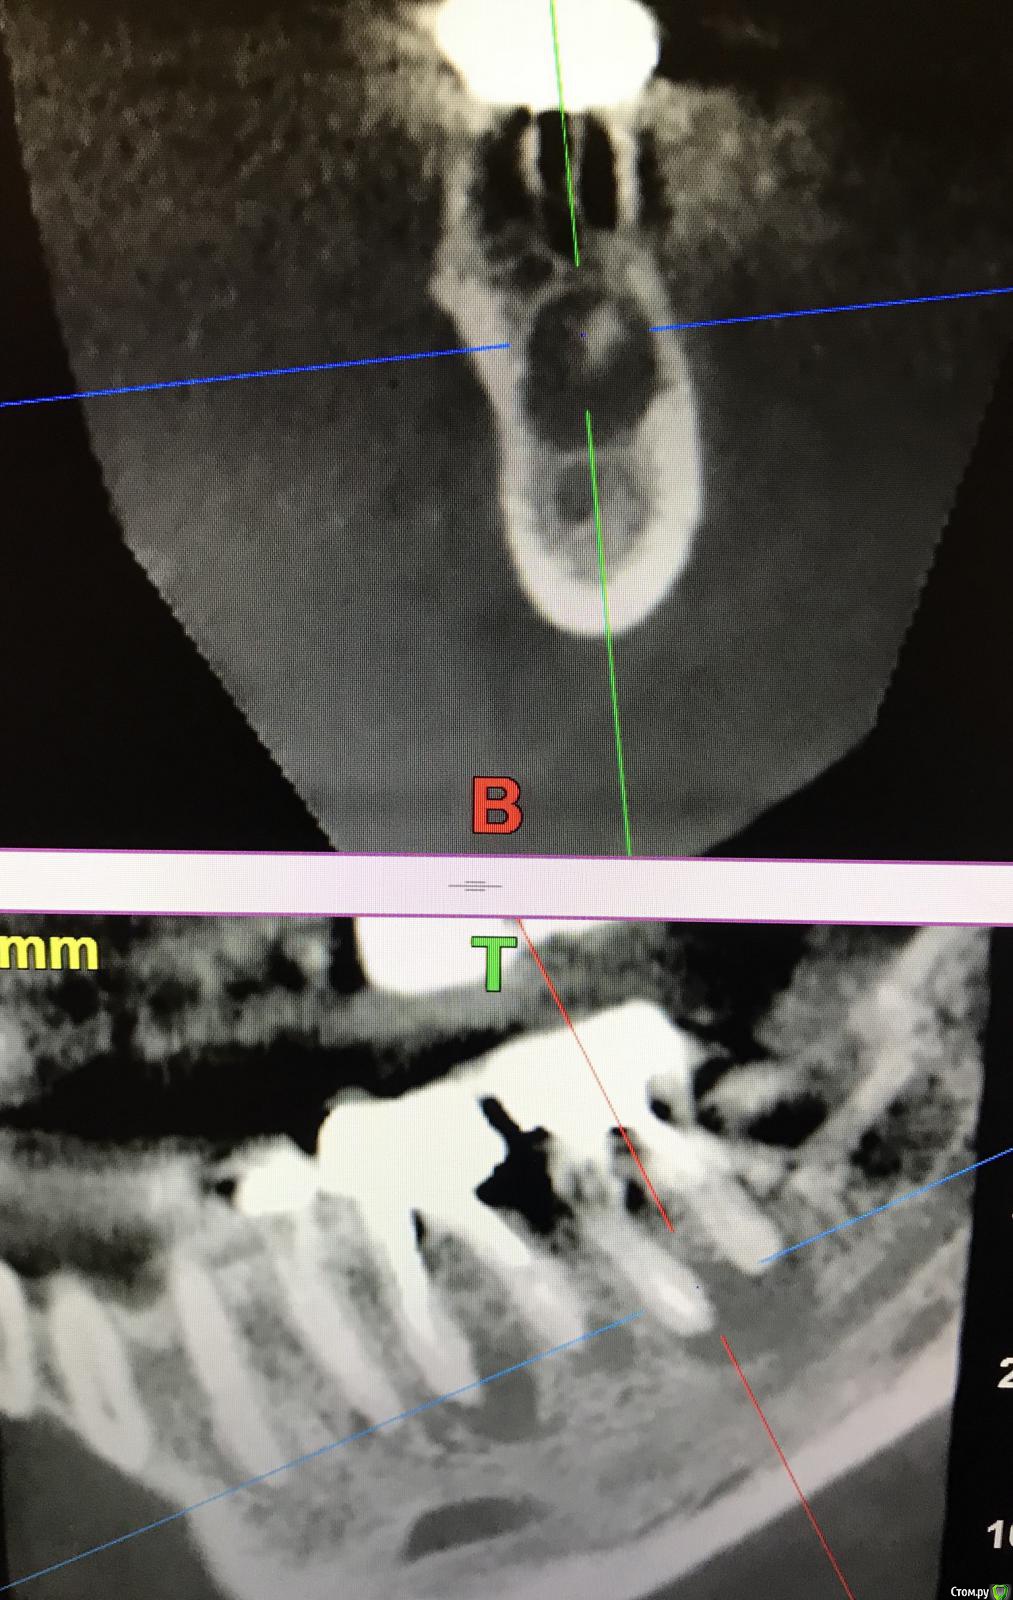

Astronaft Опубликовано 6 июля, 2018 Поделиться Опубликовано 6 июля, 2018 (изменено) Я пробовал один раз.Впечатления смешанные.1. просто в исполнении.2. Хорошо, быстро заживает. Есть ощущение что так можно проводить профилактику альвеолита.3 .Десны действительно достаточо.4. Кость - неоднозначно. Надо попробовать 2 рядом стоящих зуба "с шайбой" и "без".5. Шайба удаляется легко. Без анестетика, зондом поддел.6. Поверхность под шайбой - белая соед.тканная пленка. Рентген в день удаления -> фото через неделю -> фото через 2 месяца + КЛКТ ( срезы: перегородка и оба корня) http://miworks.weebly.com/uploads/1/6/8/7/16879370/x07221.jpg http://miworks.weebly.com/uploads/1/6/8/7/16879370/dscn6666_orig.jpg http://miworks.weebly.com/uploads/1/6/8/7/16879370/dscn6948_orig.jpg http://miworks.weebly.com/uploads/1/6/8/7/16879370/dscn6943_orig.jpg http://miworks.weebly.com/uploads/1/6/8/7/16879370/dscn6952_orig.jpg http://miworks.weebly.com/uploads/1/6/8/7/16879370/dscn6953.jpg http://miworks.weebly.com/uploads/1/6/8/7/16879370/dscn6954.jpg http://miworks.weebly.com/uploads/1/6/8/7/16879370/dscn6949_orig.jpg http://miworks.weebly.com/uploads/1/6/8/7/16879370/x07221-1.jpghttp://miworks.weebly.com/uploads/1/6/8/7/16879370/x07221-4.jpg http://miworks.weebly.com/uploads/1/6/8/7/16879370/x07221-2.jpghttp://miworks.weebly.com/uploads/1/6/8/7/16879370/x07221-3.jpg Изменено 6 июля, 2018 пользователем Astronaft 4 Ссылка на комментарий

annda Опубликовано 7 августа, 2018 Поделиться Опубликовано 7 августа, 2018 (изменено) Тоже попробовала.Застарелый перелом корня.Два свища на момент приема.Удаление всего,спилила на коронковом фрагменте до связки,канал закрыла IRMом,в дефект порошок Лилпласт на АPRF ,обратно фрагмент притопила,фиксация на ретейнер.Снимок через две недели.Теперь думаю,не длинноват ли фрагмент.Хотя,может и проекция снимка вводит в заблуждение.КТ срезы сняла с экрана,пардон за качество. Изменено 7 августа, 2018 пользователем annda 3 Ссылка на комментарий